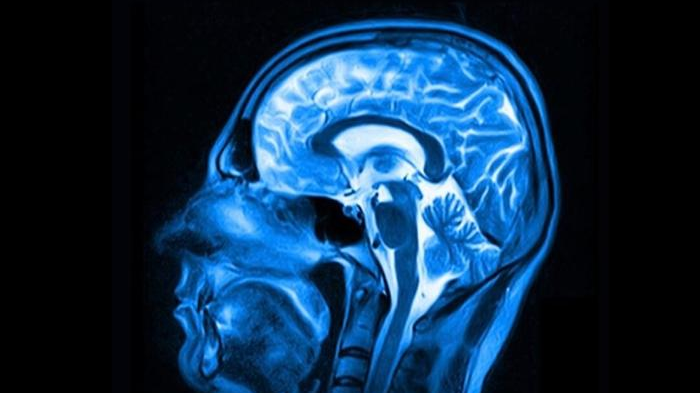

這些未經嚴格篩查的「屍體激素」,暗藏致命的朊毒體——一種能誘導腦蛋白變異的結構異常蛋白因子,最終將她的腦組織蝕成海綿狀空洞。

很快,她便無法正常握筷進食,言語也變得含糊不清,肢體完全失控,最終陷入昏迷狀態,並因呼吸衰竭而離世,整個病程前後僅歷時兩個月。經過屍檢發現,她的腦組織已被朊毒體侵蝕得猶如蜂窩狀,呈現出克雅氏病的典型病理特徵。

除了克雅氏病,科學家近年更發現這種屍體激素可能引發另一場災難。2024年《自然·醫學》研究揭露,接受c-hGH治療的患者中,多人在中年出現早發性阿茲海默病。檢測顯示,當年的激素樣本含有大量β澱粉樣蛋白和tau蛋白,正是阿茲海默病的標誌性物質。動物實驗證實,這些蛋白質能誘發腦部病變,甚至透過手術器械傳播。